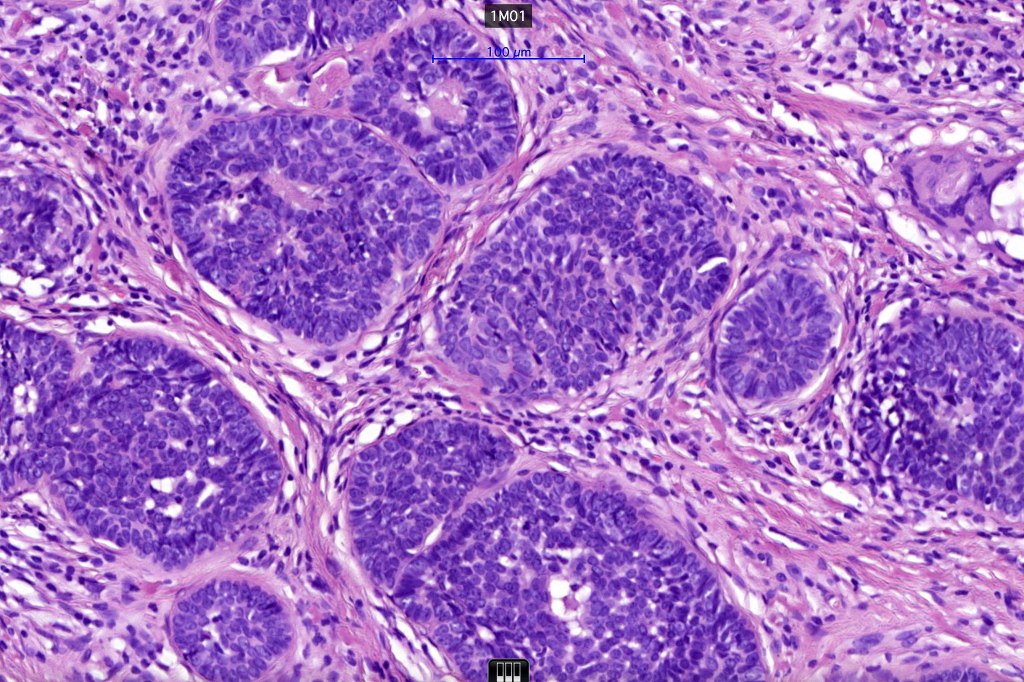

•The classical appearance consists of keratocysts & lobules of basaloid cells

•Basaloid lobules show peripheral palisading

•Perifollicular mesenchyme is always conspicuous and sometimes densely aggregated are seen indenting the baslaloid lobules (papillary mesenchymal bodies)

Trichoepithelioma should be distinguished from trichoblastoma since the latter is very rarely syndromic. Trichoepithelioma is largely a dermal tumor whereas trichoblastoma often extends from the dermis into subcutaneous fat or deeper in very large examples. Papillary mesenchymal bodies are much better formed and generally more obvious in trichoepithelioma. Trichoepithelioma must also be distinguished from basal cell carcinoma. Retraction artifact & stromal mucin are features of basal cell carcinoma and not trichoepithelioma. Papillary mesenchymal bodies are not seen in basal cell carcinoma.